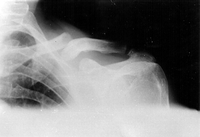

Clavicle fracture

Anteroposterior radiograph of left shoulder demonstrating a clavicle fracture

Alao D et al. Emergency Medicine Journal 2005;22:232-3; used with permission